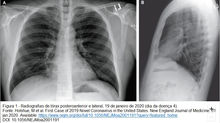

Em dezembro de 2019, um grupo de pacientes com pneumonia de causa desconhecida foi vinculado a um mercado atacadista de frutos do mar em...